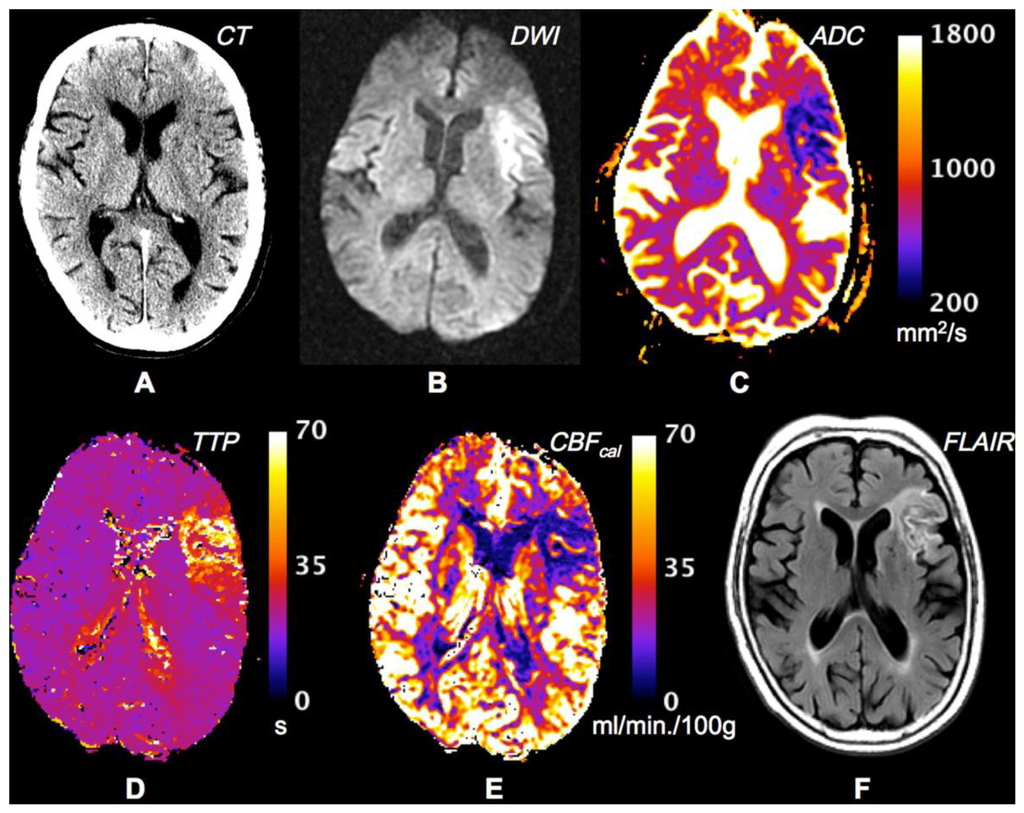

The introduction of MR diffusion-weighted imaging (DWI) and perfusion-weighted imaging opened a new era of stroke imaging and a second evolution of imaging technology was conceived from the PET based concept of penumbra to the MR based concept of mismatch. The term mismatch applies a two-compartment approach: the infarct core is delineated on maps of DWI intensity or the apparent diffusion co-efficient (ADC), and the area of low perfusion is delineated on maps of perfusion-weighted imaging (Figure 3) [61–63]. The volumetric difference of normal appearing tissue on DWI and hypoperfusion on perfusion-weighted imaging is termed “mismatch” between these two maps. The mismatch is considered at risk of infarct growth without reperfusion and shows characteristics of the penumbra. To support the concept it has been shown that the core volume correlates with stroke severity and predicts large parts of the final infarcted tissue and the rescue of so-called penumbral tissue correlates with clinical improvement [64–67]. Two types of study methodology have been used to validate the mismatch hypothesis: the first method has reviewed DWI/PWI magnetic resonance imaging to define imaging patterns that show irreversibly infarct tissue vs. salvageable tissue in the presence or absence of reperfusion. This approach utilizes large patient numbers but the longitudinal design of these studies is limited by the absence of CBF data between imaging time points [50]. The second and alternative approach that has been undertaken has compared MR findings with a “gold standard” reference method typically PET (Figure 4). Recent clinical trials using the mismatch paradigm to select patients treated with thrombolysis did not show superior outcome, further questioning the validity and utility of the paradigm for making clinical stroke management decisions [1,12,14,68]. The mismatch concept can be scrutinized by asking two broad questions: (1) Does diffusion-weighted imaging identify ischemic core; (2) Can MR mismatch reliably identify the ischemic penumbra?

Dynamic contrast perfusion-weighted imaging uses bolus tracking techniques and intravenous administration of paramagnetic contrast agents. Different curve patterns can be derived with or without deconvolution using an arterial input function obtained from large intracranial vessels such as the middle cerebral artery [77]. There are fundamental limitations with this approach. Time-to-peak (TTP), a single measure of arrival of contrast agent, does not represent the hemodynamic principle of CBF. There are other limitations. Hitherto, there is no consensus which perfusion map (TTP, relative Mean Transit Time (MTT), CBF, TMAX) most accurately identifies hypoperfusion and infarct growth or response to thrombolysis [78]. Also, superiority of deconvolved maps compared to non-deconconvolved maps has not shown to be superior in clinical studies [79,80].

To differentiate penumbra from benign hypoperfusion (oligemia) a visual analysis is inadequate. Numerous MRI thresholds have been used, including relative TTP, relative MTT, CBF and TMAX [69,79–81]. Studies that have compared PET and MR thresholds have shown large variability of a calculated mismatch according to TTP and CBF which consistently over-estimates penumbra [80,82]. A recent study shows greater concordance of MR perfusion thresholds with PET thresholds. Increase in the TTP threshold has partially improved results [82]. One of the major problems encountered is the large inter-individual variability. For the mismatch concept to be generalizable there has to be conformity on the definition applied. Up to 49 different definitions for MR mismatch and CT penumbra have been applied in the literature to date [83]. Comparative PET and MRI studies attempted to validate the mismatch hypothesis, finding that mismatch overestimated the penumbra [60,82]. There was also no agreement on the percentage of mismatch required for therapeutic decisions. The way forward for the mismatch concept has been compromised by small, unblinded studies and the absence of data from large randomized controlled trials. An arbitrary use of a volumetric difference between diffusion lesion and perfusion lesion of 20% has been used in many studies without scientific basis [50]. This is a concern because in the clinical setting patients could be inappropriately stratified by a surrogate measure of penumbra that has not been validated. Furthermore, the mismatch phenomenon may simply be difficult to identify because the penumbra determined using a single flow threshold is not capable of representing the complexity of the physiological condition. Despite these issues, proponents note that most of these studies were performed with early non-quantitative methods. More recent trials suggest there may be utility for penumbral selection when using automated, standardized, and quantitative techniques [12,84].